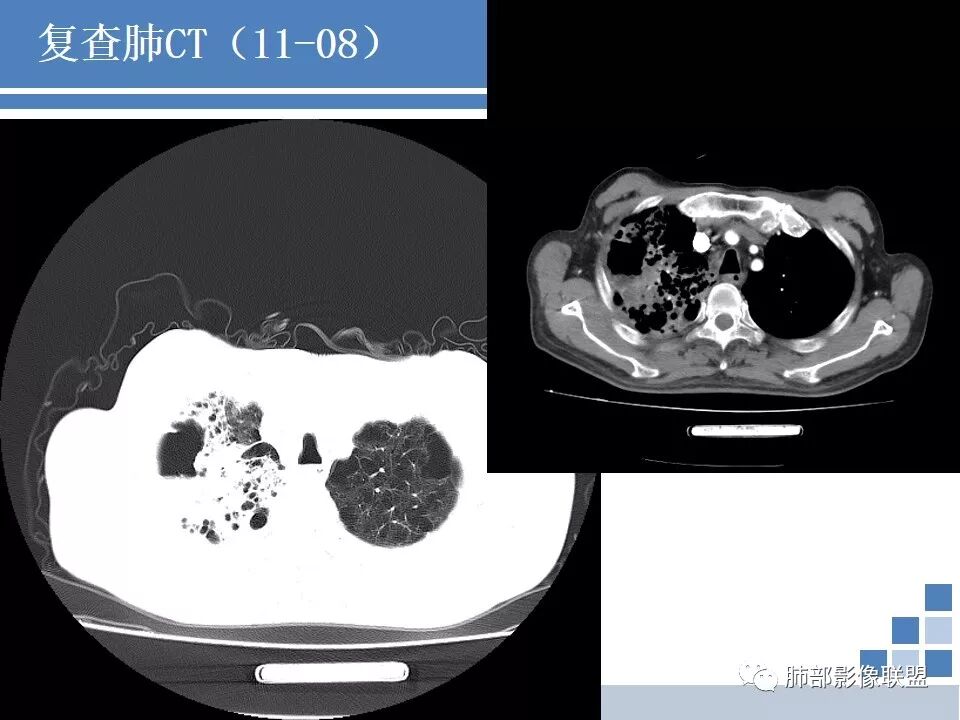

CT:肺气肿肺大泡背景,右上肺磨玻璃及实变影,10天及20天复查影像明显进展至两肺更大范围,伴右侧胸水。

晨读病例:双肺野透光度增强,胸膜下可见肺大泡。右肺上叶病灶三次影像对比病灶增大增多并出现空洞,液平。左肺上叶出现淡片状影,边缘模糊。右侧胸腔积液。考虑感染性病变,结核合并感染。

如果没有结果,分析是这样:这个人肺气肿基础,出现大片实变,那符合气肿性肺炎,头两次影像上还看不出结核来,但是白细胞不高,中性粒仅仅高一点的,然后血沉高,R干扰素高,抗感染不好。然后这个人有老年痴呆,初期可能会考虑这个人会不会只是一个细菌性肺炎呢,进展快。入院常规给与抗细菌没有问题。但是到11.08号影像出现一些端倪。一般气肿性肺炎虽然说可能好的不那么快,但是给与了亚胺培南这么高级的药反而进展,再加上血常规和一些实验室检查,好像普通细菌感染就有一点说不过去了。到第三次,出现空洞了,和肺气肿肺炎的气肿已经不一样了,气肿随着实变增加,里面应该会填实才对,但是出现空洞,这个说明不再是气肿里面的,而是真的空洞,而且还是那种肺尖的、光滑、有壁结节的空洞。